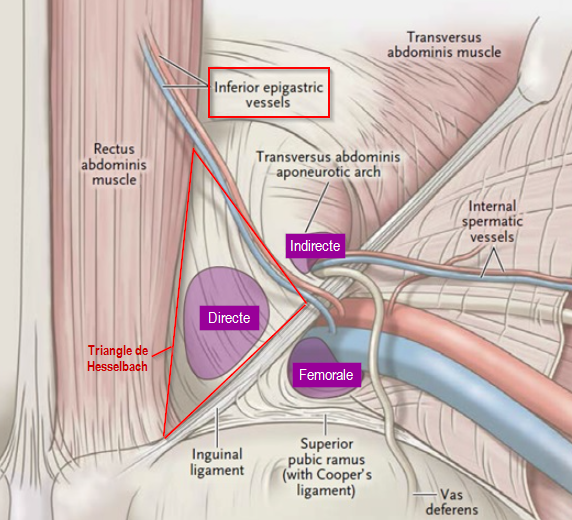

Hernies inguinales

- Repères anatomiques:

- Vx épigastriques inférieurs (les suivre depuis en haut si doute) = 1 artère 2 veines

Coupe standard

Ne pas confondre avec le cordon spermatique qui part entre deux

En vrai il y a 2 veines épigastriques inf

Hernie inguinale indirecte

Hernie inguinale directe

Hernie fémorale

Hernie fémorale